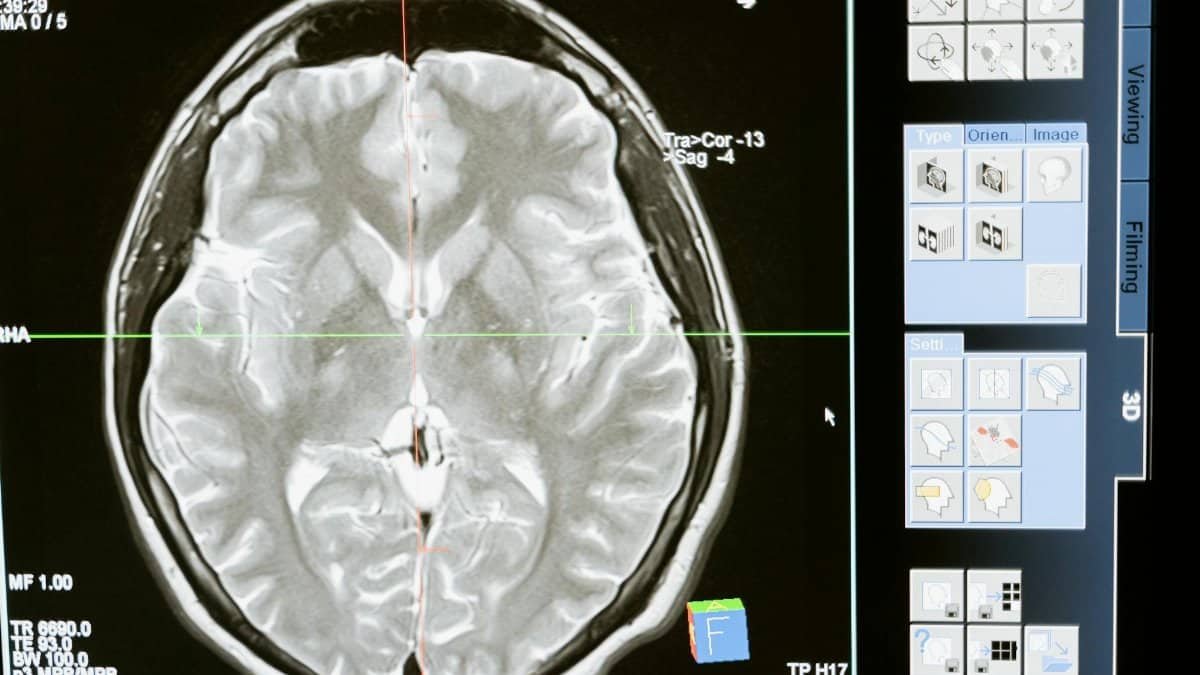

Prenuvo, through advanced MRI technology, tracks whole-body aging markers. Their December 2025 analysis flagged the brain-health pivot. Scans reveal early cognitive volume changes, prompting supplement adoption. This data-driven view positions Prenuvo as a trend authority. Their findings validate consumer moves toward nootropics, blending imaging insights with practical health advice. For more on Prenuvo’s healthspan research, see their wellness blog.